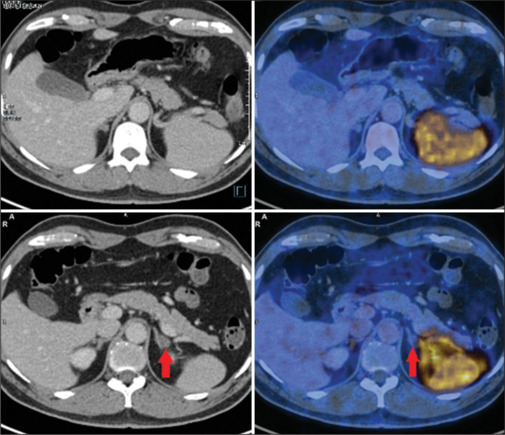

原发性醛固酮增多症(Primary aldosteronism, PA)是继发性高血压的常见病因之一,其特点是醛固酮自主分泌过多,同时肾素抑制。通过手术治疗的PA患者的临床和生化缓解率远高于通过药物治疗的患者;因此,亚型PA对于确定哪些患者将从手术中获益最大至关重要。计算机断层扫描(CT)扫描与肾上腺协议和肾上腺静脉采样(AVS)是常用的PA亚型分类。CT扫描是结构成像,不能提供功能信息,而AVS是一种侵入性的、技术上具有挑战性的方法,成功率有限,并发症风险高。C-X-C趋化因子受体4型(CXCR4)在醛固酮产生组织中过表达,但在无功能腺瘤中的表达几乎可以忽略不计。正电子发射断层扫描示踪剂68ga - pentxafor是CXCR4的特异性配体,可无创检测醛固酮产生性腺瘤,指导手术治疗。下面的图像系列展示了ga -68- pentxafor对PA亚型诊断的效用和结果模式。

Primary aldosteronism (PA) is one of the prevalent causes of secondary hypertension, characterized by the autonomous hypersecretion of aldosterone and concurrent renin inhibition. Clinical and biochemical remission rates for patients with PA achieved through surgery are far higher compared to those achieved through drug treatment; hence, subtyping PA is crucial for identifying patients who will benefit most from surgery. Computed tomography (CT) scan with adrenal protocol and adrenal venous sampling (AVS) is used conventionally for PA subtype classification. CT scans, being structural imaging, cannot provide functional information, while AVS is an invasive, technically challenging method with a limited success rate and a high risk of complications. The C-X-C chemokine receptor type 4 (CXCR4) is overexpressed in aldosterone-producing tissue but is almost negligibly expressed in nonfunctional adenoma. The positron emission tomography tracer 68Ga-pentixafor, a specific ligand for CXCR4, can detect aldosterone-producing adenoma noninvasively, which can guide surgical treatment. The image series below demonstrates the utility and patterns of findings on Ga-68-pentixafor for subtyping PA.